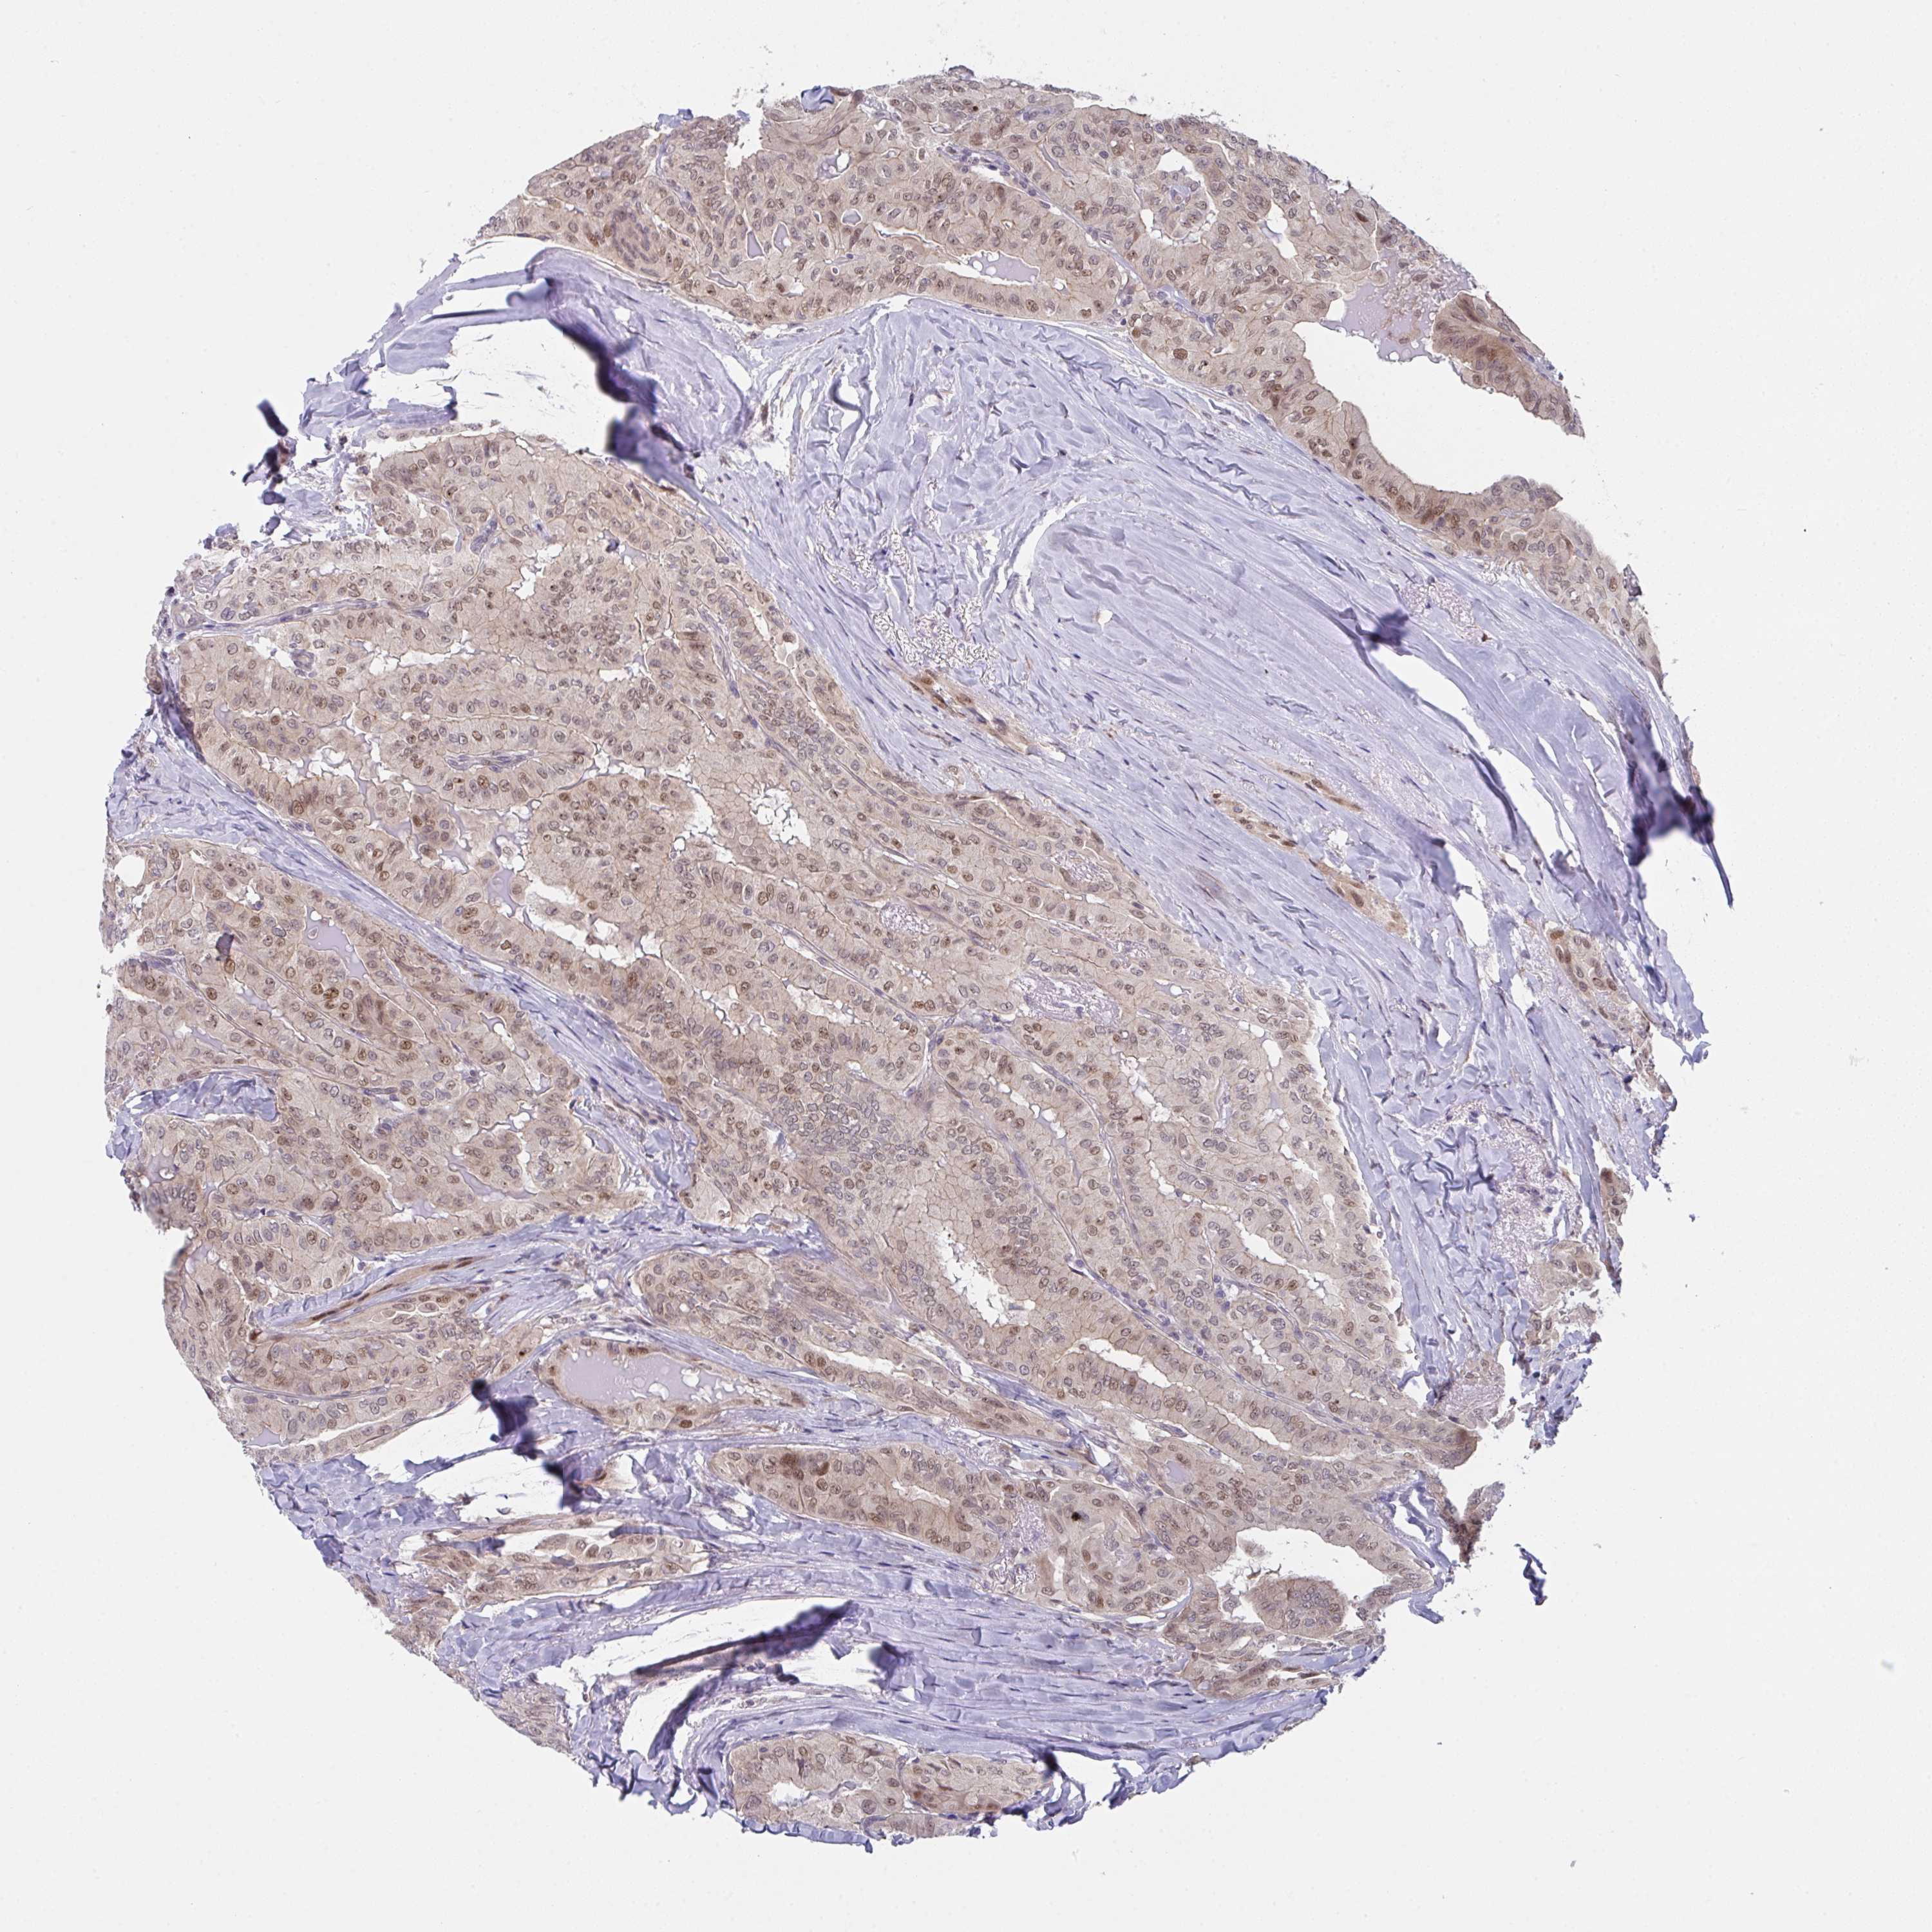

THYROID CANCER - Protein expressioni

A mouse-over function shows sample information and annotation data. Click on an image to view it in a full screen mode. Samples can be filtered based on level of antibody staining by selecting one or several of the following categories: high, medium, low and not detected. The assay and annotation is described here.

Note that samples used for immunohistochemistry by the Human Protein Atlas do not correspond to samples in the TCGA dataset.

Antibody stainingi

Antibody staining in the annotated cell types in the current human tissue is reported as not detected, low, medium, or high, based on conventional immunohistochemistry profiling in selected tissues. This score is based on the combination of the staining intensity and fraction of stained cells.

Each image is clickable and will lead to virtual microscopy that enables deeper exploration of all samples and also displays staining intensity scores, fraction scores and subcellular localization as well as patient and tissue information for each sample.

Antibody HPA057281

Staining

High

Medium

Low

Not detected

Intensity

Strong

Moderate

Weak

Negative

Quantity

>75%

75%-25%

<25%

None

Location

Nuclear

Cytoplasmic/membranous

Cytoplasmic/membranous,nuclear

Papillary adenocarcinoma, NOS

Follicular adenoma carcinoma, NOS